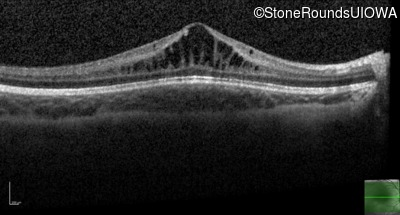

| Age at visit: 11 years |

| Age at visit: 14 years |

| Age at visit: 14 years (Visit 2) |